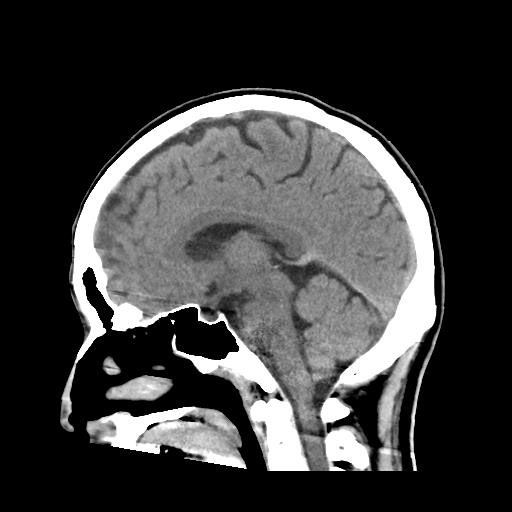

CT検査は様々な方向からX線を当て体内の水分や骨、空気など成分の違いを区別して画像を生成することで、レントゲン等では得ることができない臓器の状態を詳細に把握することが可能となり、小さい腫瘍などをより明確に映し出すことができます。

また、多角的に体内の断面図を得ることができるため立体的に構造を理解することが可能になり、病変の位置や広がりをより詳細に判断することが可能になります。